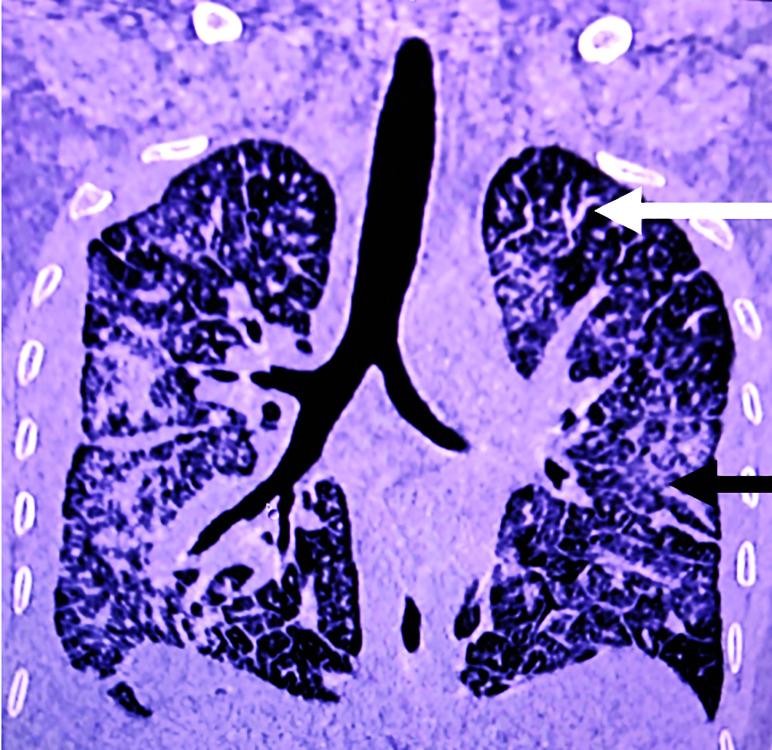

一名胃癌患者的肺肿瘤血栓性微血管病:一种罕见病症。

Pulmonary Tumor Thrombotic Microangiopathy in a Patient of Gastric Carcinoma: A Rare Entity.

Indian J Crit Care Med. 2022 Jun;26(6):763-764. doi: 10.5005/jp-journals-10071-24230.

乔杜里 S、米什拉 SB、潘达 S。一名胃癌患者的肺肿瘤血栓性微血管病:一种罕见病症。《印度重症监护医学杂志》2022 年;26(6):763 - 764。